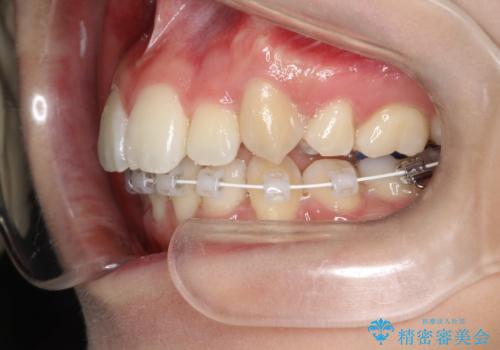

- ハーフリンガル

目立たない装置をご希望でしたので、上下左右の歯を1本ずつ抜歯してハーフリンガルでの矯正を行いました。